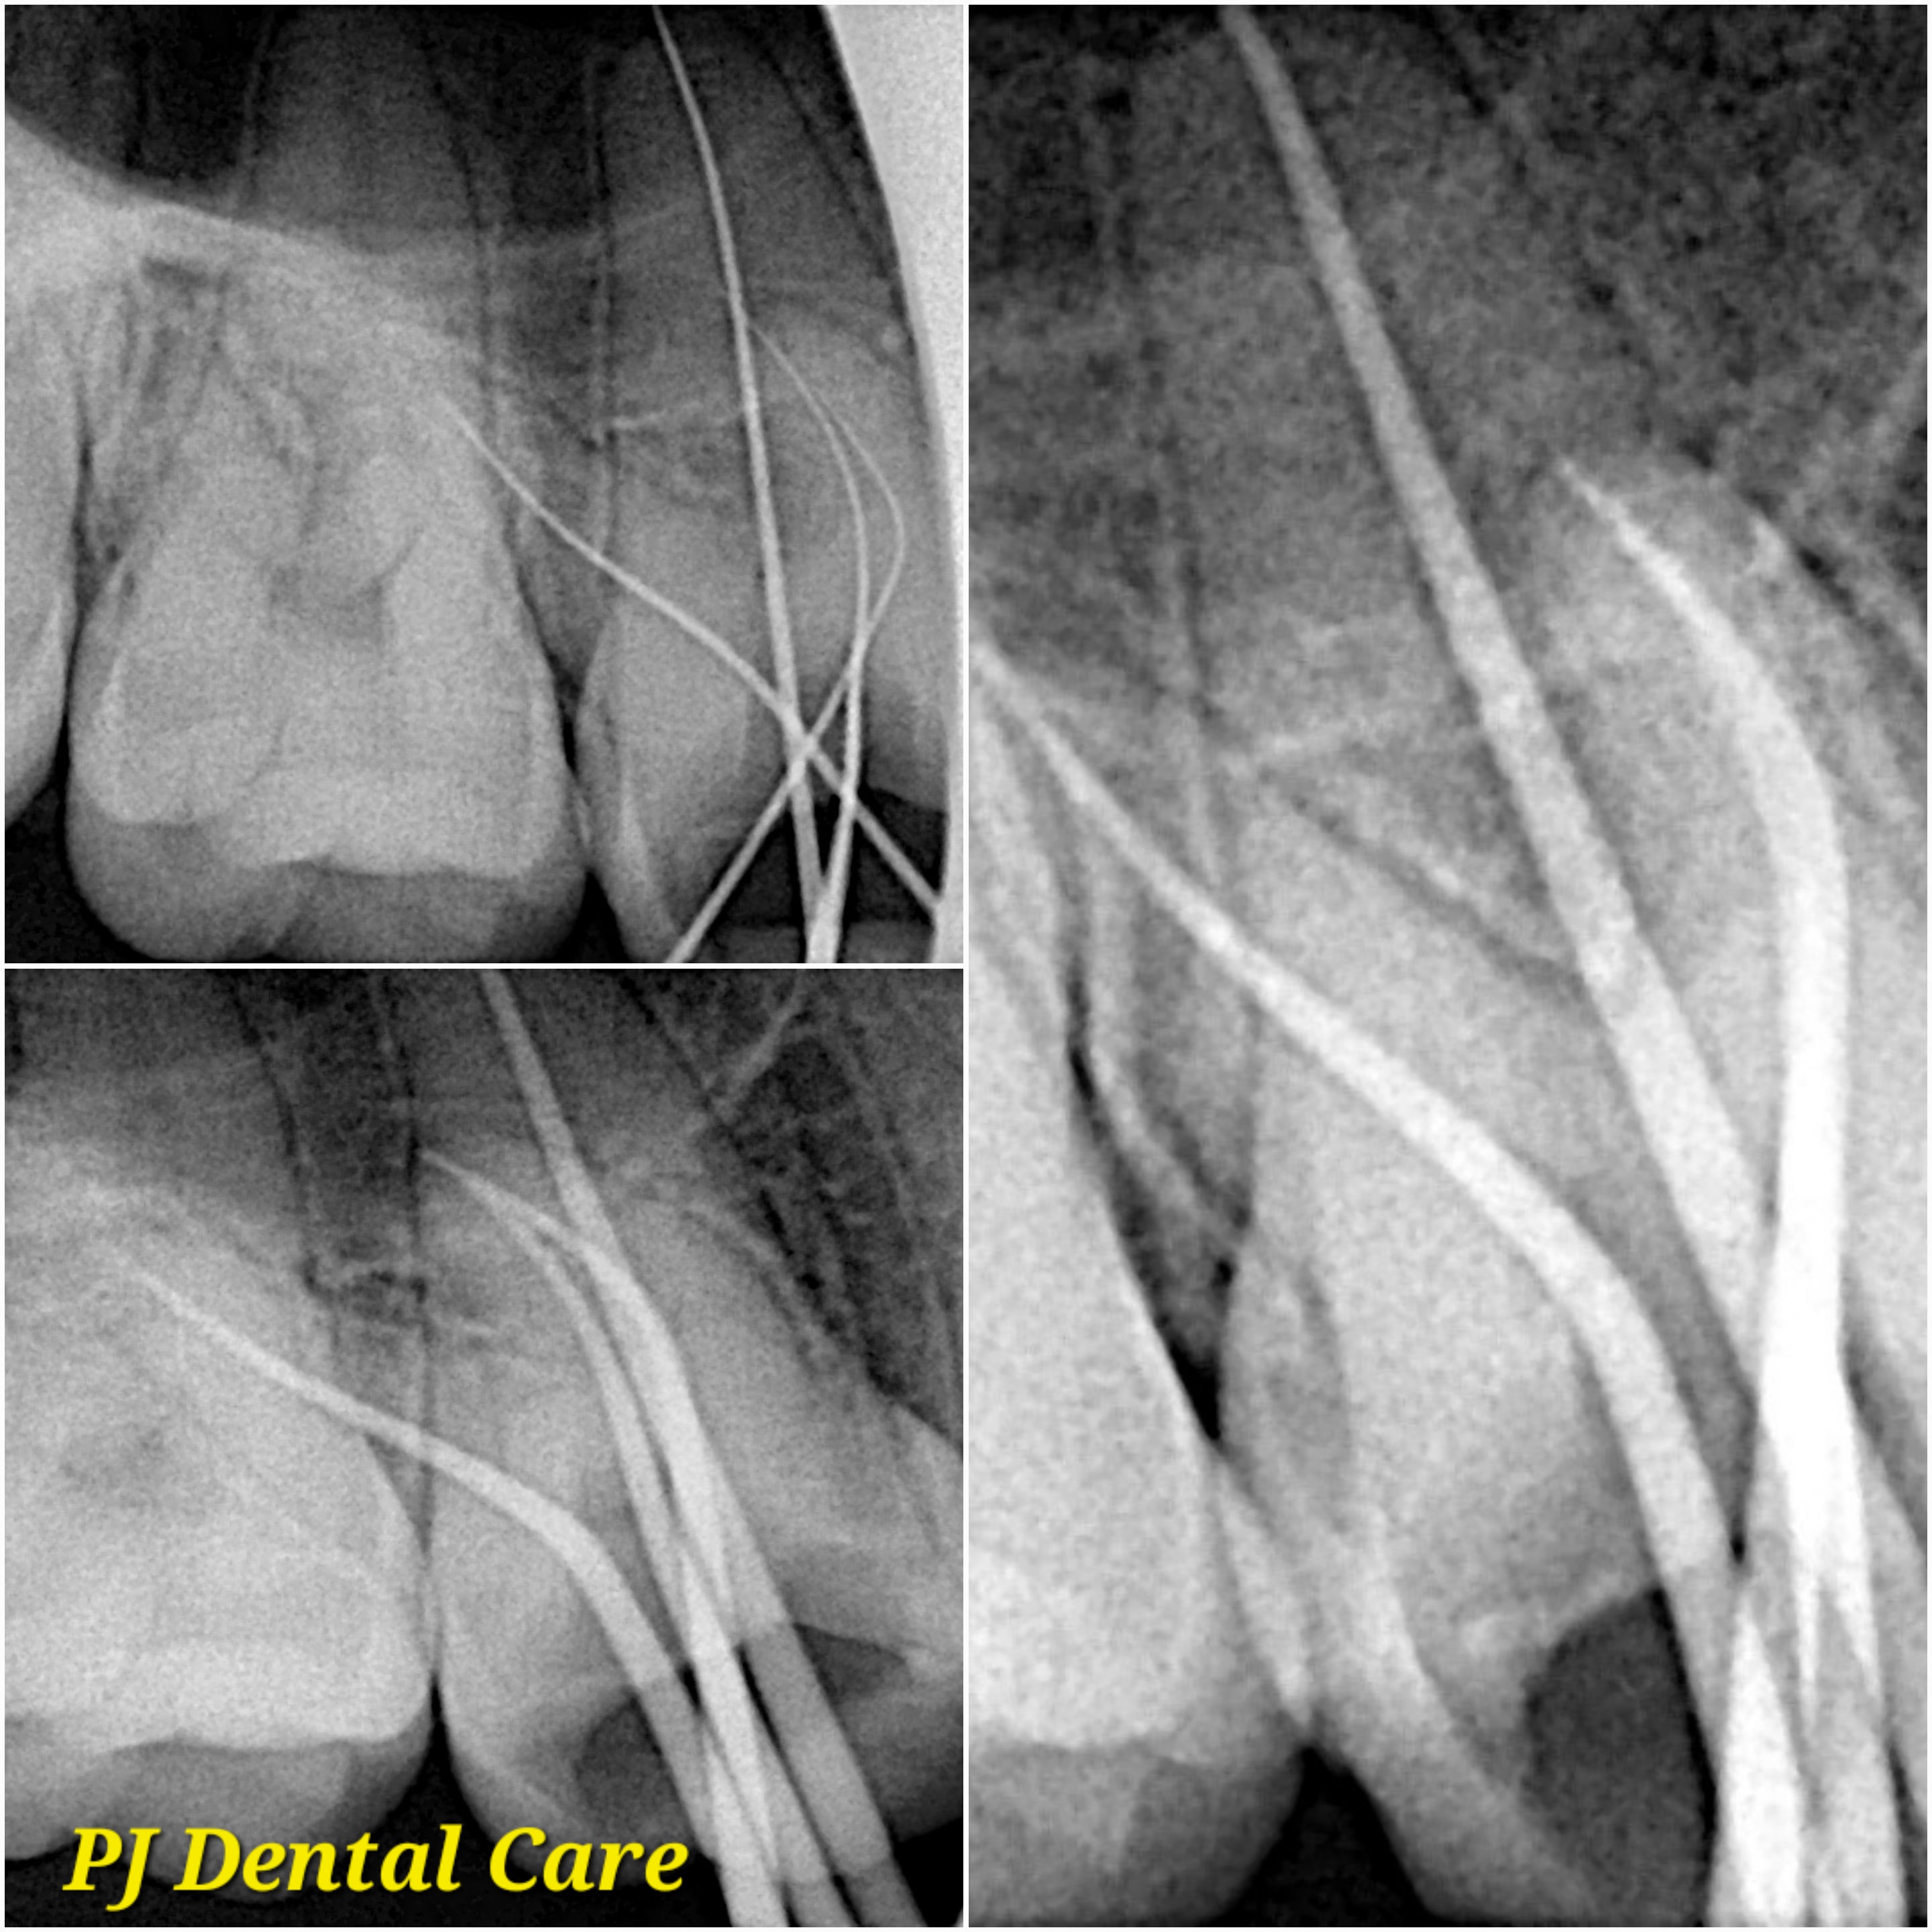

Your leading choice for dental, laser, and permanent makeup services in Tirupati. PJ Dental and Aest... hetics (Ph: 9148118616) offers affordable implants, root canals, laser hair reduction, lip blush, and more since 2012. We ensure the best treatment outcomes at reasonable prices. Read more